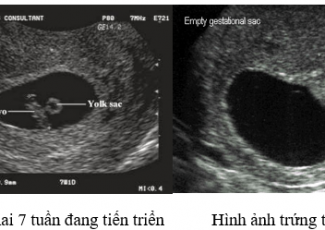

Thai nghén thất bại sớm: dấu hiệu lâm sàng và siêu âm mà bệnh nhân hiếm muộn cần biết

Với các thông tin của bài “Thai nghén thất bại sớm: dấu hiệu lâm sàng và siêu âm mà bệnh nhân hiếm muộn cần biết” sẽ giúp bệnh nhân hiếm muộn nhận biết thai của mình phát triển có bình thường hay không.